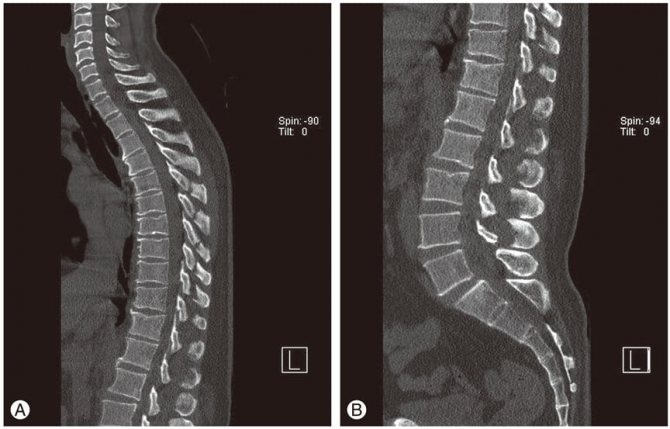

Остеофиты грудного отдела.

Деформация всего столба.

Чтобы стабилизировать шейные и грудные диски, постепенно изменяются и позвонки. Их края разрастаются, формируются костные наросты — остеофиты. При смещении они ущемляют кровеносные сосуды, мягкие ткани, спинномозговые корешки, травмируя их, усиливая интенсивность болей и тугоподвижности.

Высокие нагрузки не имеют негативного влияния на грудные позвонки, а потому остеохондроз данного участка диагностируется намного реже. Поскольку данный сегмент обладает выпуклой формой, наблюдается неравномерное распределение нагрузки. Больше всего страдают передний и боковой участки, что провоцирует появление остеофитов именно в этих местах. На задней поверхности разрастания появляются редко.

- В области разрушенных позвонков может нарастать костная ткань, которая по предположению организма должна восстановить функциональность этих позвонков. Формируются остеофиты, которые имеют неровные формы и часто выступают за пределы дисков, сдавливая нервные корешки или кровеносную артерию. Это ведет к болевому синдрому, онемению конечностей и даже временному параличу шеи, плеч, когда пациент не может сдвинуться с места.